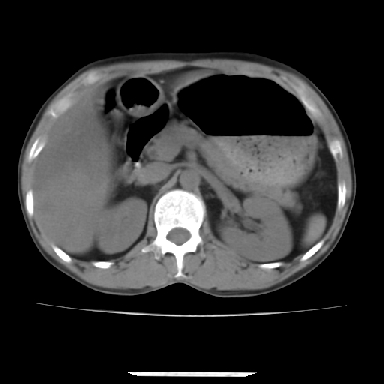

标题: CT7372:脂肪肝?外伤? [打印本页]

标题: CT7372:脂肪肝?外伤?

m 45 车祸,硬膜下血肿

窗宽太宽,调低点就好了,应该是不均质脂肪肝表现,请结合临床,单纯肝挫伤  其内无出血灶很少见,必要时做mri检查

窗宽太大,对比度太差了。局限性脂肪肝也有可能,但是亦不排除外伤性改变,增强扫描应该也还可以鉴别的。

肝内未见出血灶,但不能除外外伤性肝损伤,所示层面应考虑弥漫性脂肪肝.请结合临床必要时做mir检查

肋骨无骨折,腹腔未见游离液体,所以不均匀脂肪肝首先考虑,但如果病人情况允许还是做个增强检查放心

考虑不均匀性脂肪肝,肝包膜下光整,肋骨无异常,无腹水征,不支持肝挫伤。